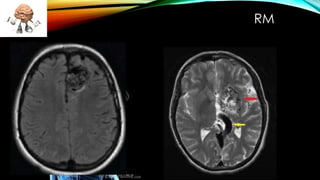

Este documento describe las malformaciones arteriovenosas, una patología vascular congénita poco común que ocurre en menos del 1% de la población. Se caracteriza por una masa retorcida y de color grisáceo que se atribuye al desarrollo anómalo del sistema venoso cerebral. Puede causar una variedad de síntomas como dolores de cabeza, convulsiones, debilitamiento muscular y problemas de visión u oído. Su diagnóstico requiere exámenes de angiografía, tomografía computarizada o resonancia magnética